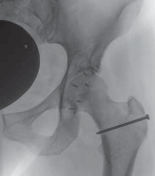

A B FIG 2•A.

Standardized AP pelvic view, showing bilateral acetabular retroversion. On the left hip the anterior (

dotted line

) and the posterior (

full line

) are outlined and form a figure-8 sign.

B.

On the lateral cross-table view, however, an important anterior bump becomes visible.